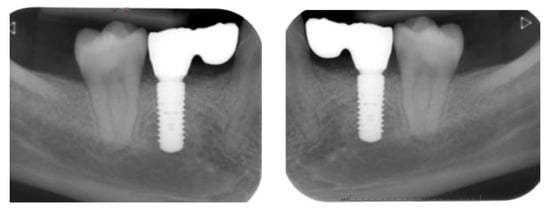

2.4.1. Radiographic Measurements

3.2. Marginal Bone Level Outcomes

| Mesial Marginal Bone Level (2D) [mm] after Immediate Placement | ||||||||

|---|---|---|---|---|---|---|---|---|

| Patient | 1 | 2 | 3 | 4 | 5 | Median | IQR | |

| Implant position | 45 | 35 | 45 | 45 | 13 | 23 | NA | NA |

| Post-OP mesial | 1.8 | 0.0 | 0.1 | 3.0 | 0.4 | 0.4 | 0.4 | 0.18–1.45 |

| 1 year mesial | 0.6 | 0.0 | 0.1 | 1.5 | 0.1 | 0.1 | 0.1 | 0.1–0.48 |

| Post-OP distal | 1.2 | 0.0 | 0.1 | 3.0 | 0.4 | 0.4 | 0.4 | 0.18–1.0 |

| 1 year distal | 0.6 | 0.0 | 0.1 | 1.5 | 0.2 | 0.0 | 0.2 | 0.03–0.5 |

| Marginal Bone Level (2D) [mm] after Delayed Placement | ||||||||

| Implant position | 35 | 45 | 35 | 35 | 35 | 45 | NA | NA |

| Post-OP mesial | 2.0 | 1.0 | 0.2 | 0.6 | 0.2 | 0.2 | 0.4 | 0.2–0.9 |

| 1 year mesial | 1.6 | 0.5 | 0.0 | 0.3 | 0.1 | 0.1 | 0.3 | 0.1–0.45 |

| Post-OP distal | 0.0 | 0.5 | 0.0 | 0.6 | 0.1 | 0.1 | 0.1 | 0.03–0.4 |

| 1 year distal | 0.0 | 0.2 | 0.0 | 0.3 | 0.1 | 0.1 | 0.1 | 0.03–0.18 |